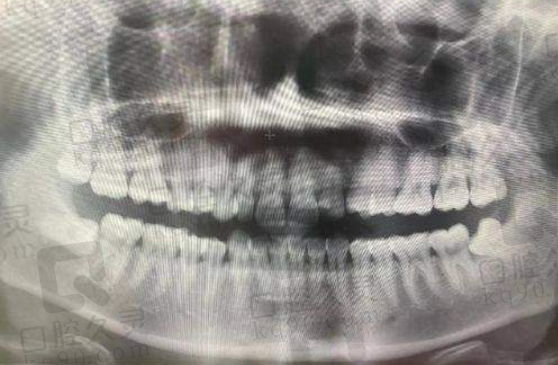

长了上颌智齿,疼起来那叫一个要命,想去拔牙又怕费用太高?别担心,无锡美奥口腔给你送补贴啦!他家上颌智齿拔牙价格180元起,收费合理,而且营业时间长,就诊超方便!下面就带大家详细了解一下。

无锡美奥口腔的上颌智齿拔牙价格特别有优势。其中,上颌简单智齿拔除180元起。不过呢,智齿的情况不一样,价格也会有所不同。像2025年1月1日的信息显示,上颌智齿500元起一颗,上颌正位智齿拔除也是500元起/颗;到了2025年1月14日,上颌正位智齿拔除300元起/颗。这说明,具体的价格得根据智齿的生长状况来定。

其次,医院的设备特别精良。拔牙可不是一件小事,需要精细的操作和专精的设备。无锡美奥口腔引进了精良的口腔诊疗设备,能够正确判断智齿的位置和生长情况,为拔牙手术提供有力的支持。